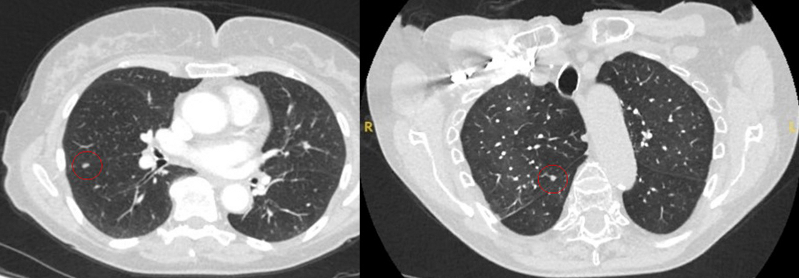

The appearance of the adjacent fissure, as well as any visible pleural ‘tags’, are signs that need to be considered when evaluating perifissural or peripheral solitary lung nodules. A retracted fissure associated with a non-smooth nodule increases the possibility of malignancy.[33][34][Figure caption and citation for the preceding image starts]: Computed tomography (CT) sections from two cases with benign perifissural nodules. Note the smooth margins and the normal undisturbed adjacent fissureFrom the collection of Dr George Tsaknis, MD, PhD, FRCP(London), MRQA, MAcadMEd, PGCert; used with permission [Citation ends].